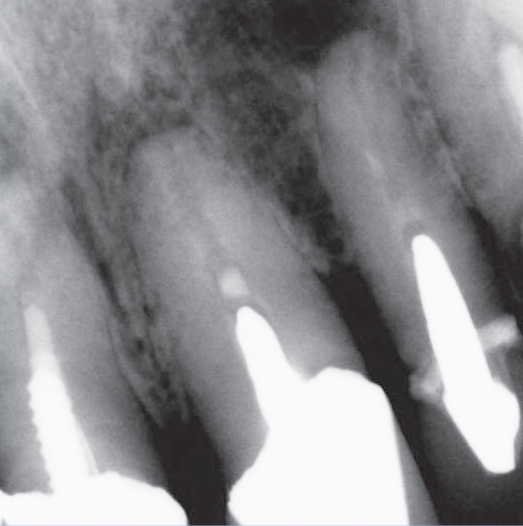

After

After Root Canal treatment